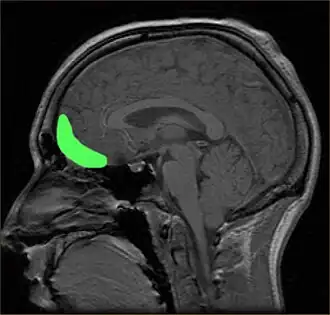

Areas of the brain linked to the processing of visual aesthetics

Aesthetic perception relies heavily on the processing by the visual centers in the brain such as the V1 cortex. Signals from V1 are distributed to various specialized areas of the brain.[51] There is no single area where all specialized visual circuitry connect, reducing the chances of determining a single neural center responsible for aesthetics, rather a neural network is more likely.[8] Therefore, the visual brain consists of several parallel multistage processing systems, each specialized in a given task such as color or motion. Functional specializations of the visual brain are already known.[44]

Physiological phenomenon can explain several aspects of art appreciation. Different extrastriate areas of the visual cortex may have evolved to extract correlations of different visual features. The discovery and linking of various visual stimuli is facilitated and reinforced by direct connections from these areas to limbic structures. Additionally, art may be most appealing if it produces heightened activity in a single dimension rather than redundant activation of multiple modules, restricted by the allocation of attentional resources.[10] In experimentation to determine specific areas, many researchers allow the viewer to decide the aesthetic appeal prior to the use of imaging techniques to account for the varying perceptions of beauty. When individuals contemplate the aesthetic appeal, different neural processes are engaged than when pragmatically viewing an image.[23] However, processes of object identification and aesthetic judgment are involved simultaneously in the overall perception of aesthetics.[23]

Prefrontal cortex

The prefrontal cortex is previously known for its roles in the perception of colored objects, decision making, and memory. Recent studies have also linked it to the conscious aesthetic experience because it is activated during aesthetic tasks such as determining the appeal of a visual stimuli. This may be because a judgment is needed, requiring visiospatial memory. In a study performed by Zeki and Kawabata, it was found that the medial orbito-frontal cortex (mOFC) is involved in the judgment of whether a painting is beautiful or not.[44] There is high activation in this region when a person views paintings which they consider beautiful. Other evidence shows that this same area is active during the experience of beauty derived from different sources,[55] including musical beauty[56] and moral beauty,[57] and even mathematical beauty.[58] Experience of the sublime, as opposed to the beautiful, results in a different pattern of brain activity;[59] moreover, where it comes to judgment, although aesthetic and perceptual judgments leads t activity in the same brain areas, the pattern of activity is also different between the two, one of the most marked differences being the involvement of mOFC in aesthetic, but not in perceptual, judgments.[60] Surprisingly, when a person views a painting which they consider ugly, no separate structures are activated. Therefore, it is proposed that changes in the intensity of activation in the orbito-frontal cortex correlate with the determination of beauty (higher activation) or ugliness (lower activation).

Conversely, activity in the motor cortex showed the opposite pattern.[61] Additionally, the medial OFC has been found to respond aesthetics in terms of the context of which it is presented, such as text or other descriptions about the artwork. The current evidence linking the OFC to attributed hedonistic values across gustatory, olfactory, and visual modalities, suggests that the OFC is a common center for the assessment of a stimulus's value.[47] The perception of aesthetics for these areas must be due to the activation of the brain's reward system with a certain intensity.

Additionally, the prefrontal dorsalateral cortex (PDC) is selectively activated only by stimuli considered beautiful whereas prefrontal activity as a whole is activated during the judgment of both pleasing and unpleasing stimuli.[8] The prefrontal cortex may be generally activated for directing the attention of the cognitive and perceptual mechanisms towards aesthetic perception in viewers untrained in visual arts.[23] In other words, related directly to a person viewing art from an aesthetic perception due to the top-down control of their cognition. The lateral prefrontal cortex is shown to be linked to higher order self-referential procession and the evaluation of internally generated information. The left lateral PFC, Brodmann area 10, may be involved in maintaining attention on the execution of internally generated goals associated with approaching art from an aesthetic orientation.[23]